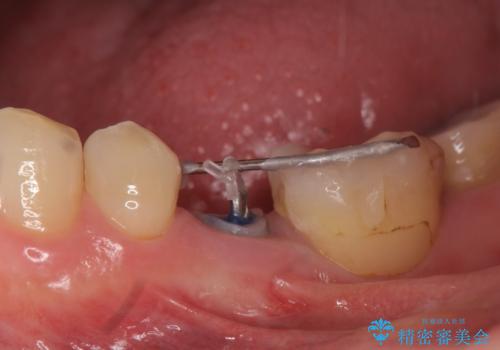

- 左下の奥歯がズキズキ痛むので診て欲しいといらっしゃった方の症例です。他院では5番目と7番目の歯を抜歯してインプラントと言われたが、出来れば歯を残したいとのことでした。

痛みの原因は6番目の虫歯であること、5番目、6番目の歯は歯茎より深い虫歯であり現状では保存が難しいことを説明した上で、歯を挺出させる部分矯正と歯茎を下げる歯周外科を行いました。

手術後歯茎の治癒を待ち、オールセラミッククラウンによる補綴を行いました。